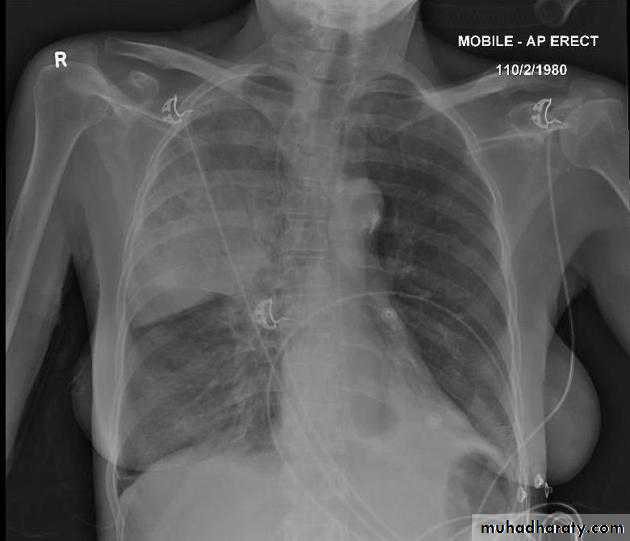

Left lower lobe collapse has distinctive features, and can be readily identified on frontal chest radiographs, provided attention is paid to the normal cardiomediastinal contours. The shadow cast by the heart does however make it harder to see than the right lower lobe collapse

Radiographic features

Left lower lobe collapseis readily identified in a well penetrated film of a patient with normal sized heart, but can be challenging in the typical patient with collapse, namely unwell patients, with portable (AP) often under-penetrated films, often with concomitant cardiomegaly. Features to be observed include :

triangular opacity in the posteromedial aspect of the left lung

edge of collapsed lung may create a 'double cardiac contour'

left hilum will be depressed

loss of the normal left hemidaphgragmatic outline

loss of the outline of the descending aorta

Non-specific signs indicating left sided atelectasis are usually also be present including:

elevation of the hemidiaphragm

crowding of the left sided ribs

shift of the mediastinum to the left